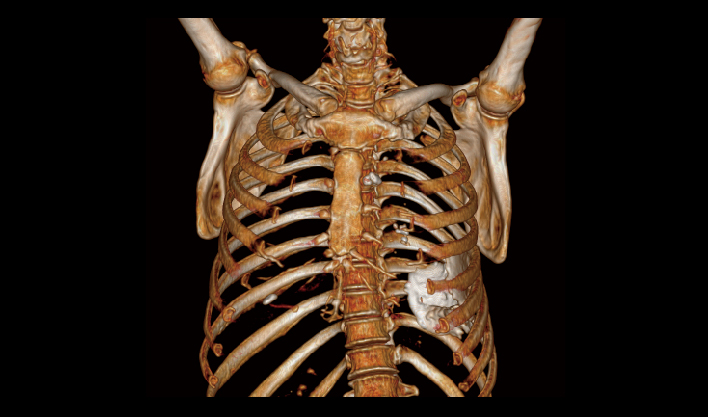

El detector de área amplia, combinado con la rotación de alta velocidad, garantiza imágenes de alta resolución y minimiza los artefactos de movimiento.

El detector de cuerpo ancho de cuarta generación, de desarrollo propio, cubre más áreas de tejido.

La matriz de reconstrucción de 1024*1024 amplía los datos de la imagen cuatro veces. Combinado con imágenes de corte fina, incluso las lesiones más invisibles son claramente visibles.

Captura instantánea para evitar artefactos por movimiento respiratorio, lo que mejora la tasa de éxito de los exámenes.